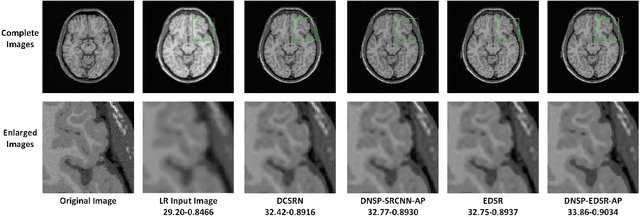

Abstract:High resolution Magnetic Resonance (MR) images are desired for accurate diagnostics. In practice, image resolution is restricted by factors like hardware and processing constraints. Recently, deep learning methods have been shown to produce compelling state-of-the-art results for image enhancement/super-resolution. Paying particular attention to desired hi-resolution MR image structure, we propose a new regularized network that exploits image priors, namely a low-rank structure and a sharpness prior to enhance deep MR image super-resolution (SR). Our contributions are then incorporating these priors in an analytically tractable fashion \color{black} as well as towards a novel prior guided network architecture that accomplishes the super-resolution task. This is particularly challenging for the low rank prior since the rank is not a differentiable function of the image matrix(and hence the network parameters), an issue we address by pursuing differentiable approximations of the rank. Sharpness is emphasized by the variance of the Laplacian which we show can be implemented by a fixed feedback layer at the output of the network. As a key extension, we modify the fixed feedback (Laplacian) layer by learning a new set of training data driven filters that are optimized for enhanced sharpness. Experiments performed on publicly available MR brain image databases and comparisons against existing state-of-the-art methods show that the proposed prior guided network offers significant practical gains in terms of improved SNR/image quality measures. Because our priors are on output images, the proposed method is versatile and can be combined with a wide variety of existing network architectures to further enhance their performance.

Abstract:High resolution magnetic resonance (MR) images are desired for accurate diagnostics. In practice, image resolution is restricted by factors like hardware, cost and processing constraints. Recently, deep learning methods have been shown to produce compelling state of the art results for image super-resolution. Paying particular attention to desired hi-resolution MR image structure, we propose a new regularized network that exploits image priors, namely a low-rank structure and a sharpness prior to enhance deep MR image superresolution. Our contributions are then incorporating these priors in an analytically tractable fashion in the learning of a convolutional neural network (CNN) that accomplishes the super-resolution task. This is particularly challenging for the low rank prior, since the rank is not a differentiable function of the image matrix (and hence the network parameters), an issue we address by pursuing differentiable approximations of the rank. Sharpness is emphasized by the variance of the Laplacian which we show can be implemented by a fixed {\em feedback} layer at the output of the network. Experiments performed on two publicly available MR brain image databases exhibit promising results particularly when training imagery is limited.